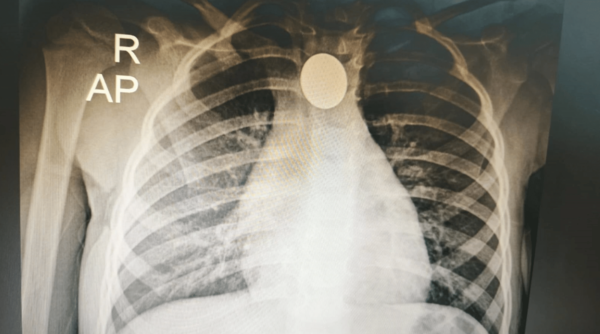

Niña salvada tras tragarse una moneda en Roque Alonso

Médicos del Ineram salvan a niña de 3 años que tragó una moneda. Exitosa intervención de emergencia en Paraguay. ...[Leer más]